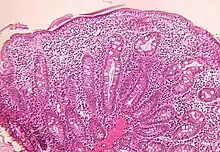

Small intestine biopsy of a patient with THE syndrome showing severe villous atrophy with intense mononuclear cell infiltration in the lamina propria. (Courtesy of Prof. Michel Peuchmaur, Hôpital Robert Debré, Paris, France)

Microscopic examination of a biopsy of the small bowel in these patients shows villous atrophy with low or no mononuclear cell infiltration of the lamina propria nor specific abnormalities involving the epithelium. The amount of villous atrophy does not explain the severity of the diarrhea.